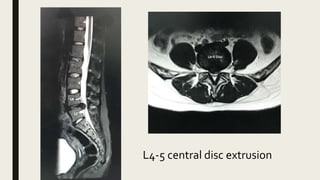

L4-5 central disc extrusion